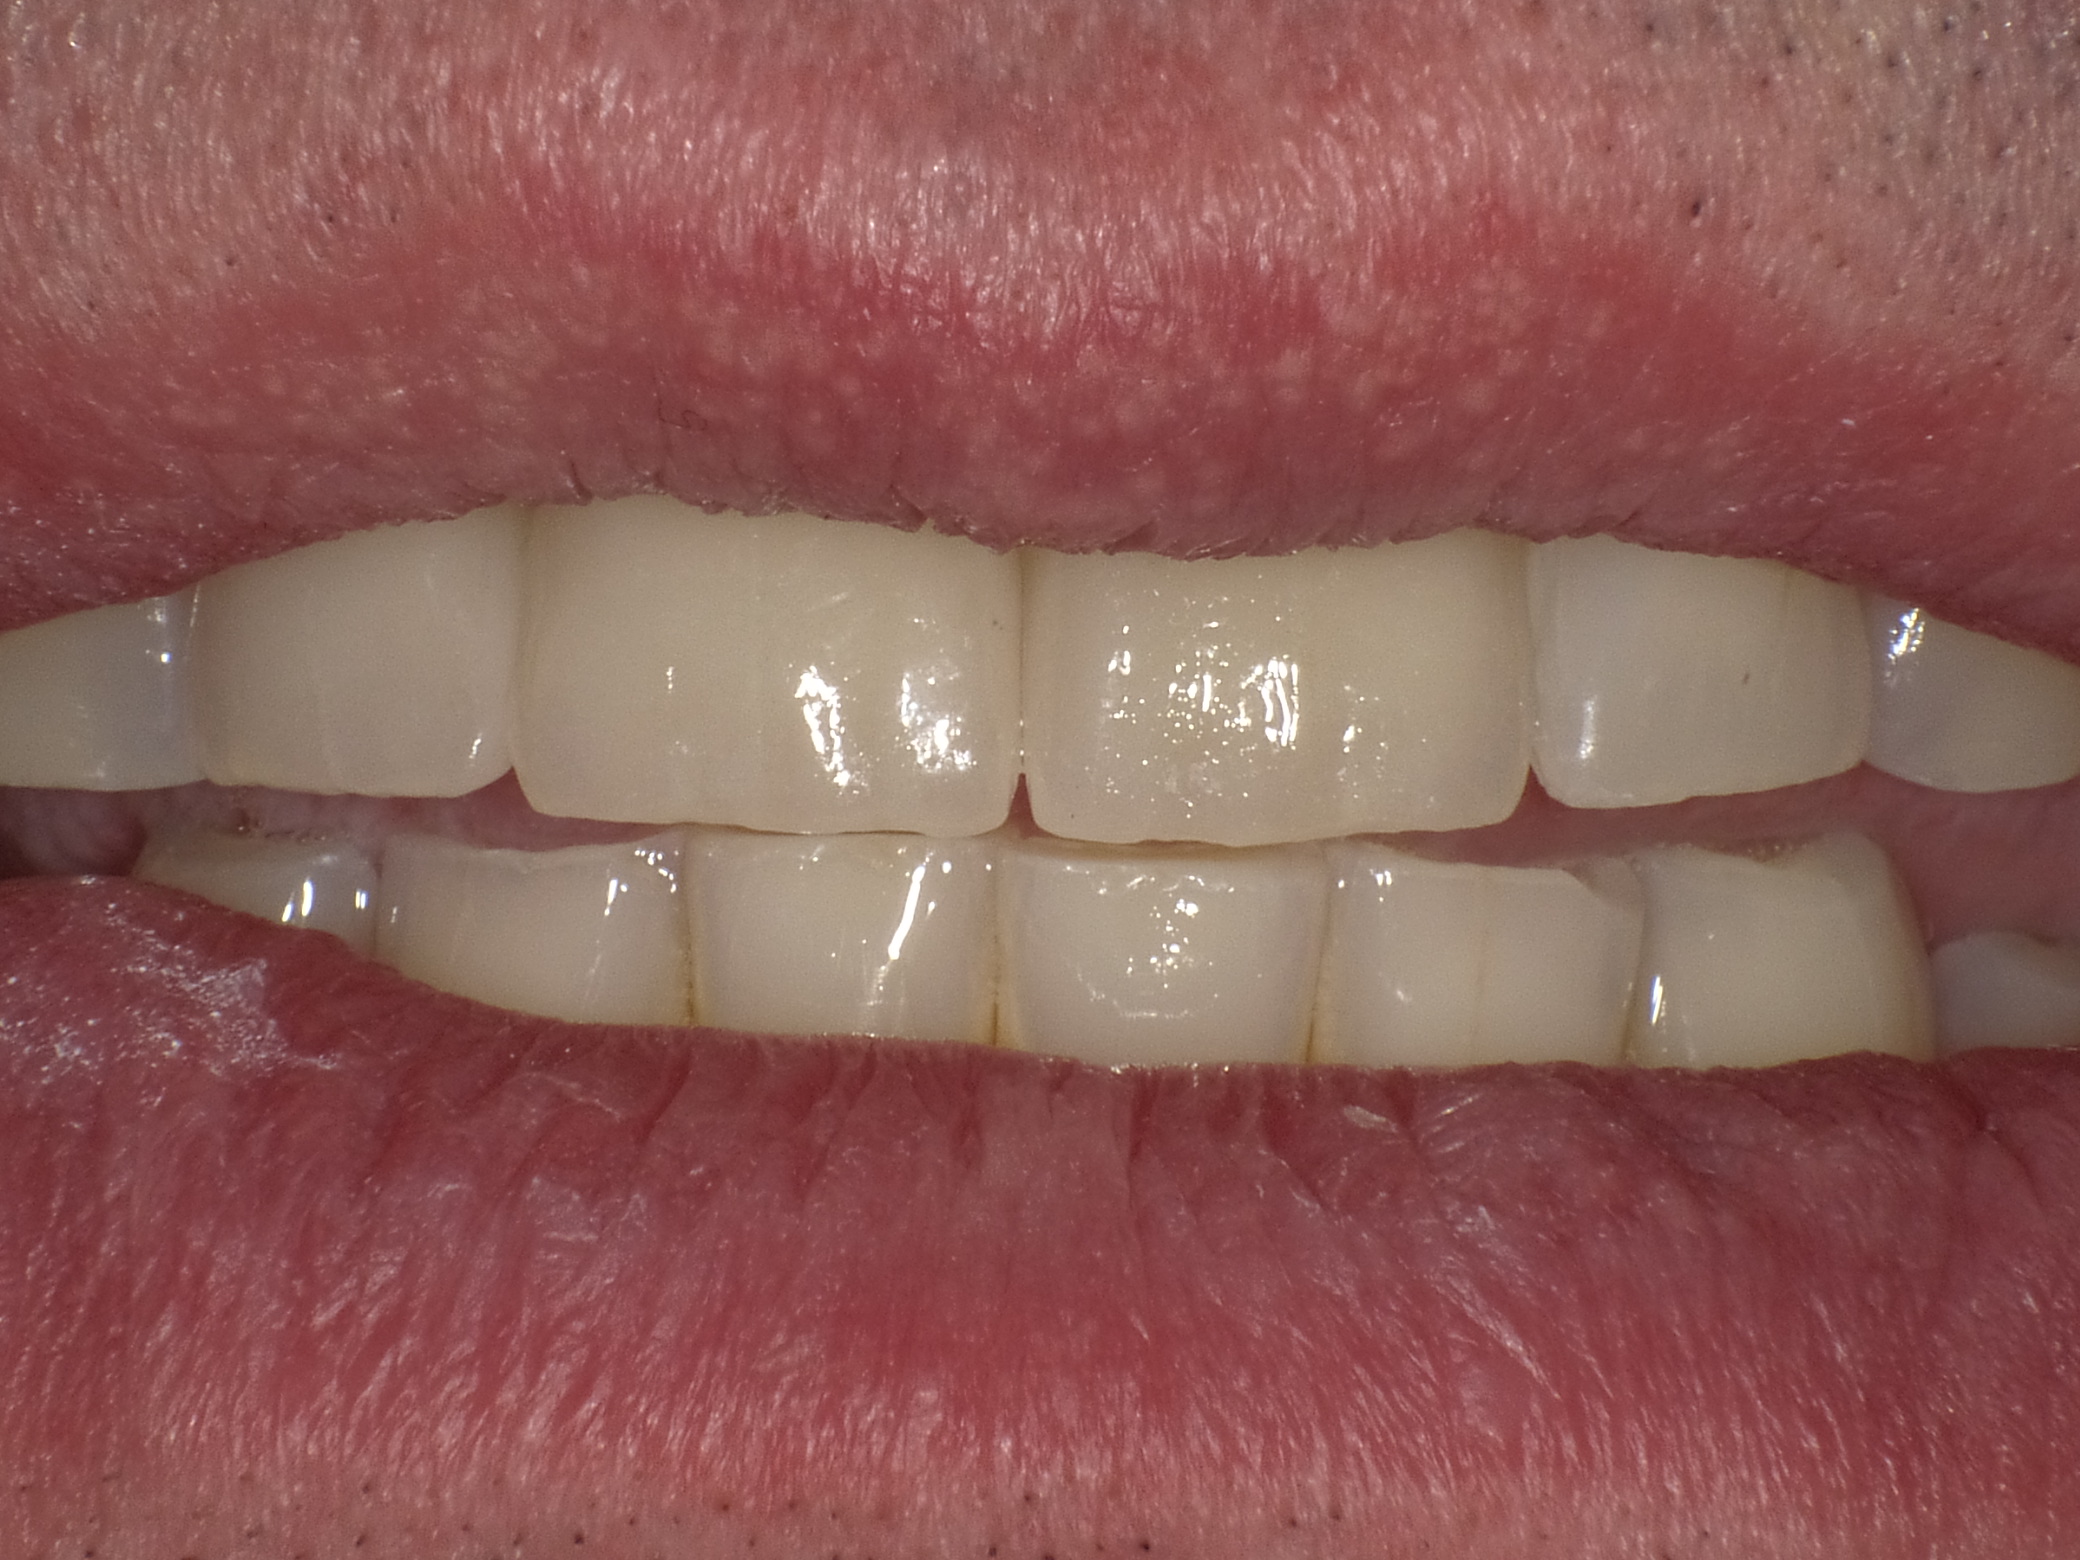

Unbefriedigende Ästhetik, vor allem aber Entzündungen im Knochen und eine massive Parodontitis mit bereits gelockerten Zähnen

Vorher: Unbefriedigende Ästhetik, vor allem aber Entzündungen im Knochen und eine massive Parodontitis mit bereits gelockerten Zähnen

Gesamtbehandlung in Sedierung: die Seitenzähne wurden durch Keramik-Implantate (Zahnentfernungen und Sofortimplantation) mit Knochenaufbau ersetzt; anschließend Gesamtüberkronung aus Vollkeramik mit Optimierung der Ästhetik

Nachher: Gesamtbehandlung in Sedierung: die Seitenzähne wurden durch Keramik-Implantate (Zahnentfernungen und Sofortimplantation) mit Knochenaufbau ersetzt; anschließend Gesamtüberkronung aus Vollkeramik mit Optimierung der Ästhetik